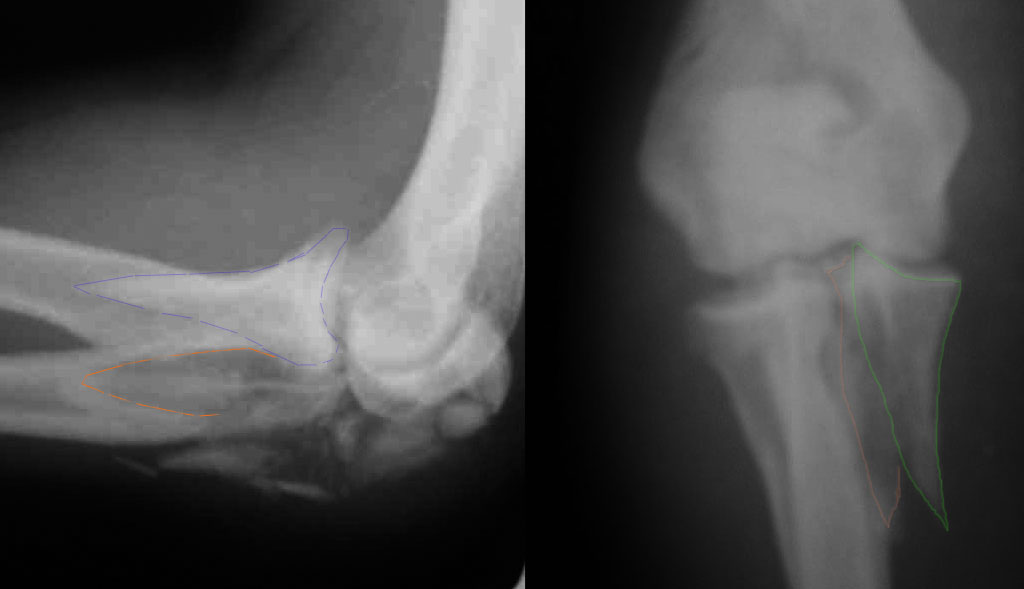

При самом большом к Вам уважении, Сергей Анатольевич, не соглашусь. У меня, после того, как добавили "прямой" снимок, сомнений не осталось. Венечный сломан наверняка. Но чтобы судить, насколько это критично для стабильности, нужно иметь строго боковую проекцию. И при этом помнить, что на него крепятся медиальные связки.

Прикрепляю снимок, где обведен фрагмент, несущий на себе венечный отросток (весь он смещён с этим фрагментом или частично - без качественной боковой проекции судить сложно), и отдельно на снимке обведено "ложе", от которого он сместился.

Как минимум два фрагмента, включающих суставную поверхность, и много (т.е. более двух) околосуставных осколков метафиза

В начале недели видел снимок (больного -нет). Конечно, венечный отросток сломан. Сложности возникают из-за небольших размеров верхушки локтевого отростка и первичного дефекта. Не везде имеются специальные пластины. Мы обходимся обычной трубчатой пластиной + проволочная петля. Снимки, похожие, выложу позднее (необходимо отредактировать).